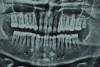

The final restorations depicted restoration of form, function, and beauty, with good harmony of restoration and the periodontium (Figure 19 through Figure 25). MIP was in harmony with CR, and right and left lateral excursion discluded all posteriors with anterior group function. The postoperative orthopantomogram (OPG) (Figure 26) shows the treatment done while maintaining the vitality of anterior teeth.

Figure 26. Postoperative OPG; note the vitality of the anterior teeth.

Figure 26